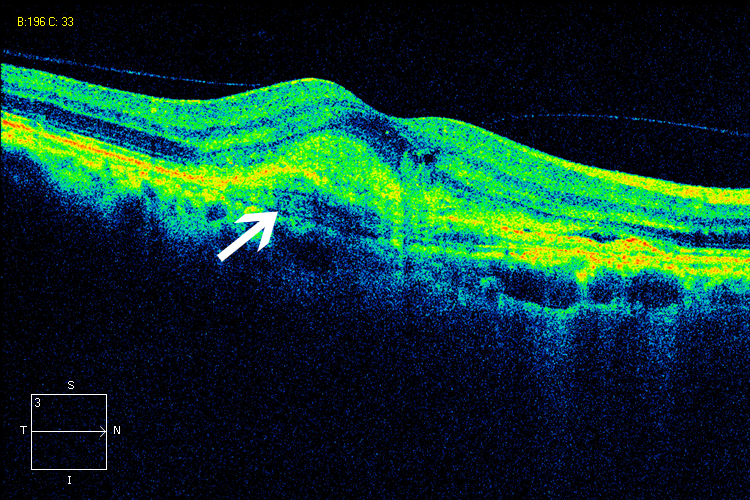

眼科ab超检查单怎么看常见眼底疾病检查结果的秒懂解读_https://www.jmylbn.com_新闻资讯_第14张

OCT:视网膜神经纤维层呈红色、黄色高反射(中箭头),其下方水肿,呈遮蔽暗区(短箭头)

图片来源:天津市眼科医院